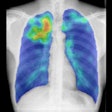

COVID-19_FDG_PET_CT_JNM_Albano_Image_G_400.png?auto=format%2Ccompress&fit=crop&h=112&q=70&w=112)